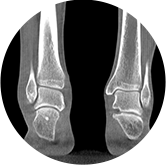

足踝

關閉金屬偽影校正

開啟金屬偽影校正